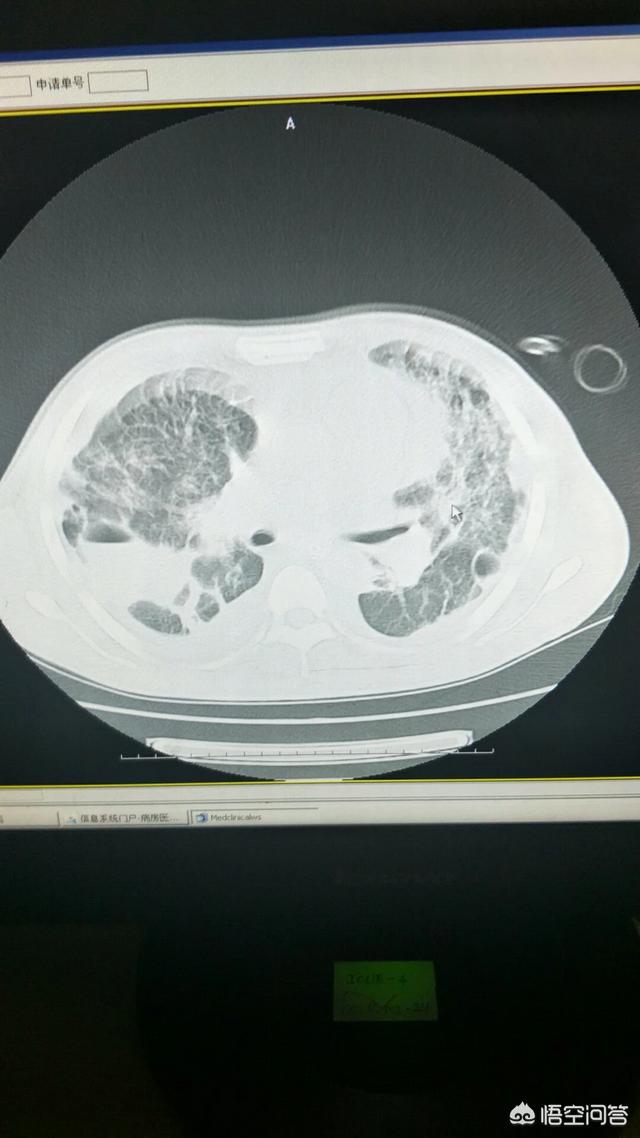

结核分为肺结核、肾结核、肠结核、输卵管结核、关节和脊柱结核等等。

在这里主要谈一谈肺结核的主要症状:

包括呼吸系统本身的症状以及全身症状

先谈一谈呼吸系统本身的症状

1、肺结核最常见的呼吸系统是咳嗽咳痰

2、咯血:大部分患者为少量咯血,发生大咯血的患者不多

3、结核侵犯胸膜可引起胸痛,咳嗽或者呼吸时胸痛加重

4、并发肺炎或者大量胸腔积液患者可出现呼吸困难